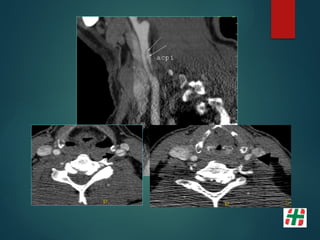

Disección Vascular

 Causa frecuente de Stroke isquémico en adultos jóvenes.

 Desgarro de la pared con formación de hematoma mural.

 Multifactorial, Trauma, infecciones, etc.

 Determinar extensión.

Mayor indicación de la secuencia TOF. Valor del crudo.